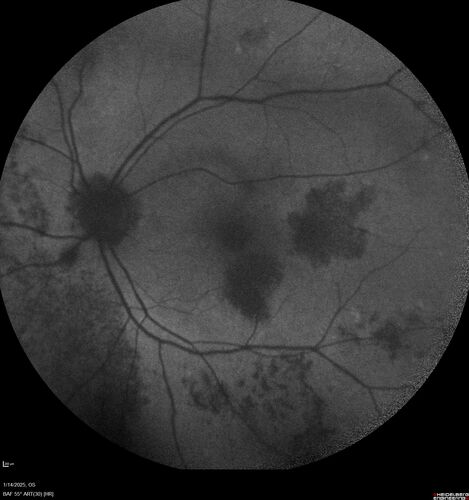

Birdshot Chorioretinitis - Chronic Untreated with Drusen Like Material in Macula

72 year old female with vision changes for years just now diagnosed with Birdshot.